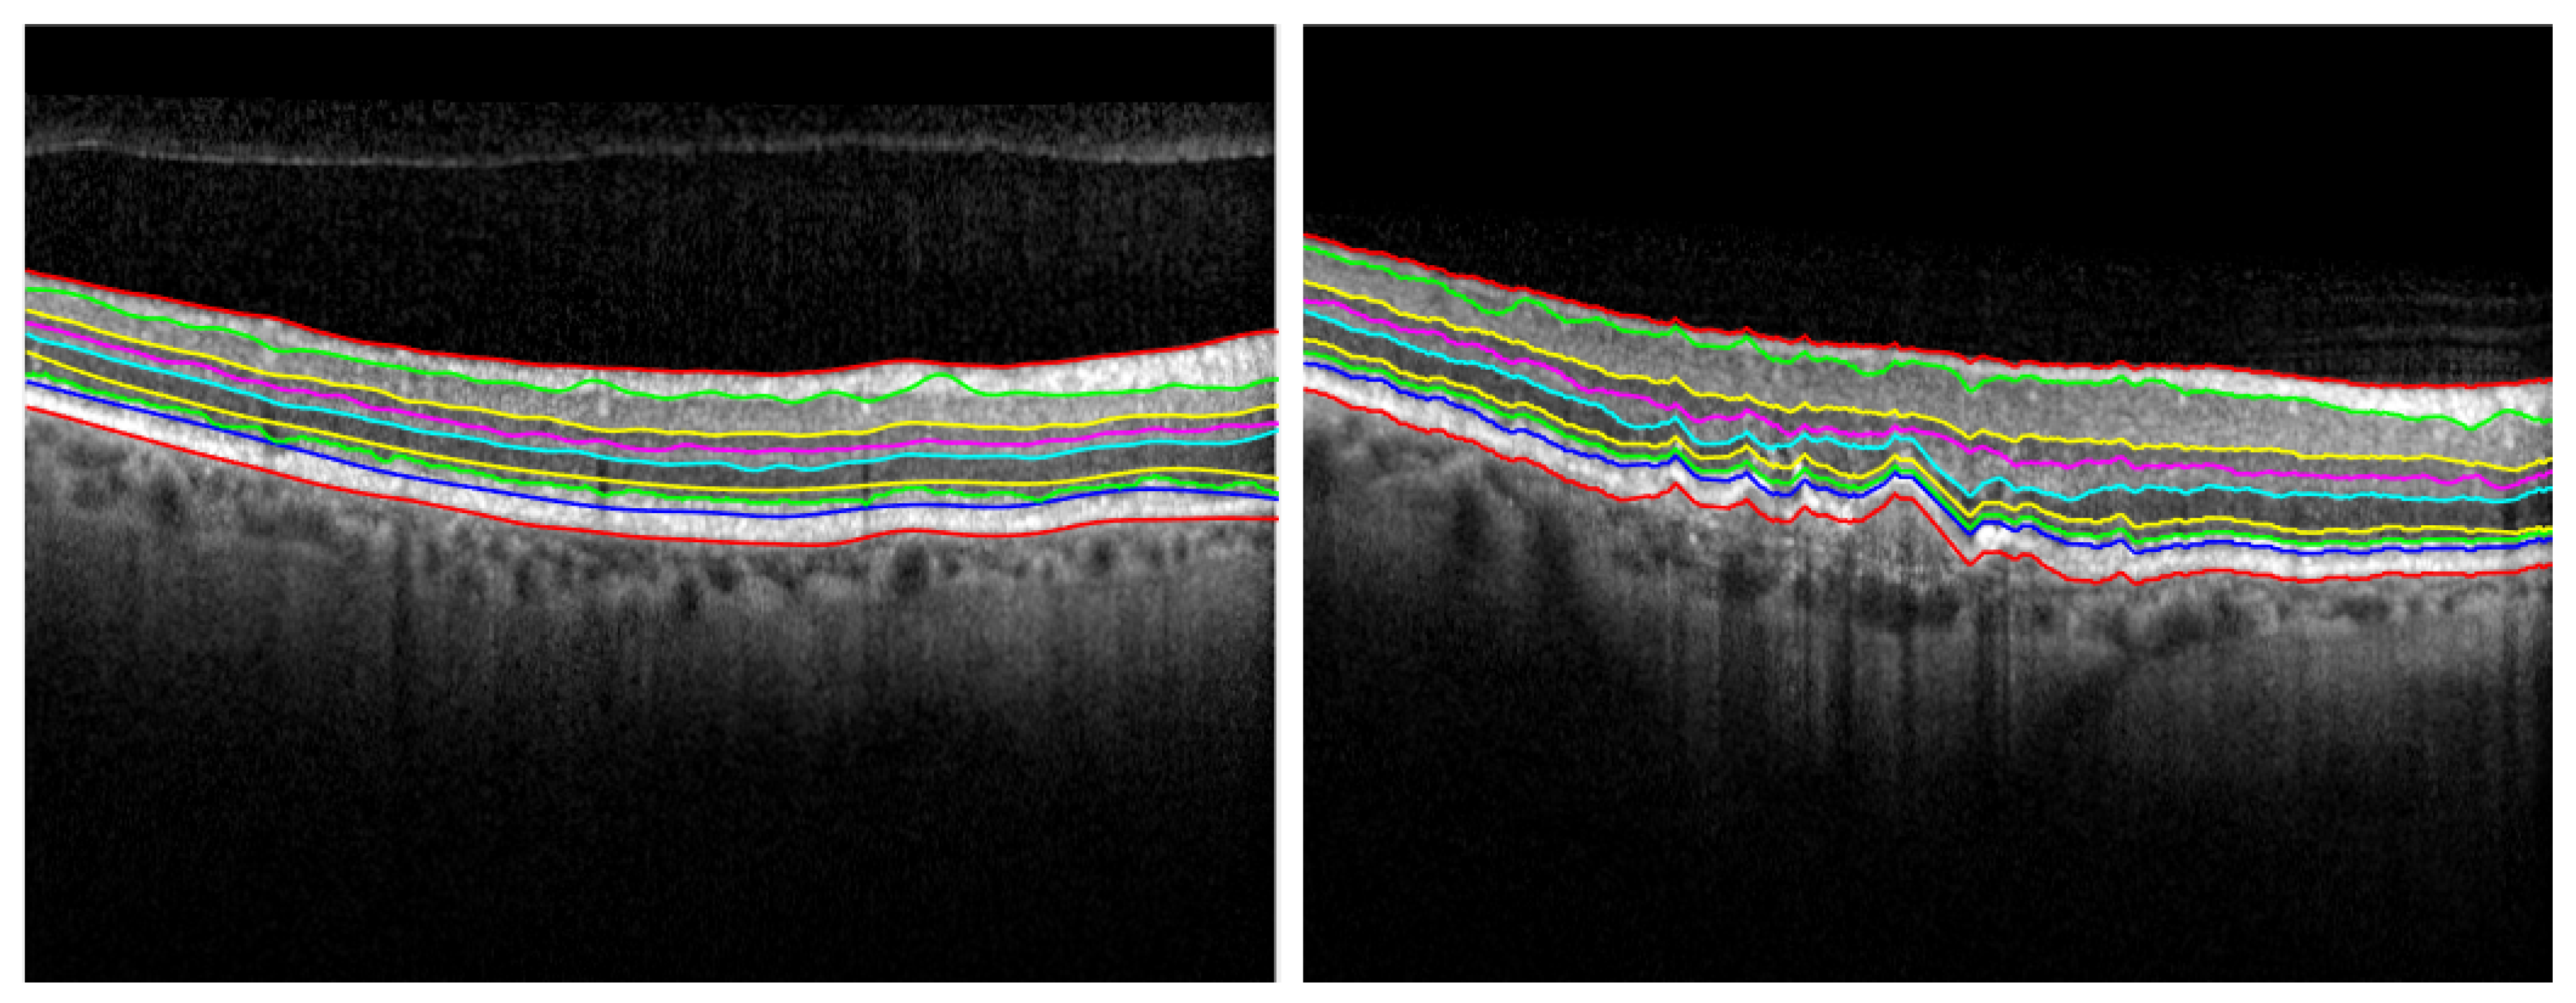

After detecting the IS-OS layer, it is important to limit the search for boundaries for the remaining layers to only be in the areas of interest for each specific boundary. Therefore, a human agent is able to preview the regions of interest of these new frontiers, which are sequentially calculated based on the previously segmented layers (see Figure 4). Then, the human-in-control can assess if the regions are correctly overlapping the layer which needs to be segmented.

If the areas of interest do not match the corresponding layer, the human agent can modify the parameters and call the function again on the adjusted parameters. The frontiers are obtained with the function g e t S e g B o u n d a r y applied on the image computed by multiplying the gradient map with the binary mask of the area of interest of the current edge. The results of the algorithm are illustrated in Figure 5.

Figure 4. Computing the areas of interest for each layer: B2, B4, B6 and B7 (left) and B1, B3, B5 and B8 (right).

Diagnostics 12 00022 g004

Figure 5. Retinal segmentation on a healthy retina on the left side, while segmentation of a pathological retina is presented on the right.

Diagnostics 12 00022 g005